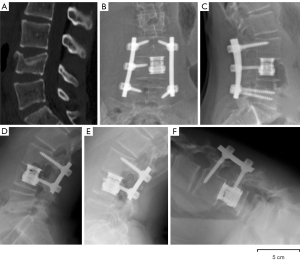

A 13-year-old female was treated for a burst (Dennis) Type B Fracture at L4 secondary to a 3 m fall in sports climbing activities. Surgical treatment was decided upon as more than one third of the height of the vertebral body is affected. She had no neurological deficit. A transpedicular L4 corpectomy and anterior L3/4 fusion with a cage was performed by posterior approach associated with a posterior L3/5 fixation (10) (Figure 1). Postoperative course was uneventful. The patient underwent a rehabilitation protocol with physiotherapy at a rate of 2 sessions per week for 5 weeks. The objective was to rehabilitate walking, reduce pain and improve lumbar mobility. All procedures performed in studies involving human participants were in accordance with the ethical standards of the institutional and/or national research committee(s) and with the Helsinki Declaration (as revised in 2013). Written informed consent was obtained from the patient for publication of this case report and accompanying images. A copy of the written consent is available for review by the editorial office of this journal.

After assessment of the L3/4 anterior fusion by a CT-scan at 1 year, the L5 posterior fixation was removed. The patient had not undergone rehabilitation with physiotherapy. Ultrasound elastography of the anterior annulus fibrosus were performed according to an already validated protocol (9,11) (Figure 2). Shear Wave Speed (SWS) was measured in the anterior part of the annulus fibrosus of L4/5 and L5S1 discs. Three clips of about 10 s (about 10 elastography frames per clip) were recorded for each disc, i.e., L4/5 and L5/S1. The average SWS value was calculated in each region of interest to obtain a single SWS value (from three clips × 10 frames = 30 frames per disc) for L4/5 and L5/S1. The size of the region of interest (ROI) was also adapted to the disc and to the elastographic signal, to avoid signal saturation or missing signal. ROI was between 1 and 3 cm2. Acquisitions were performed, by the same operator, one year after fracture treatment (before L5 fixation removal), then 6 months and 1 year after L5 fixation removal. Frontal and lateral X-rays were also acquired at each time point of the treatment. Dynamic flexion-extension bending films were done 1 year after L5 fixation removal. Two years after L5 fixation removal, the patient was symptoms-free and had a normal function. Dynamic X-rays showed a restoration of disc mobility at the L4/5 level without signs of instability or disc degeneration (Figure 1). Although SWS was within the normality corridor before removal of L5 fixation, it decreased at 6 months and 1 year after L5 fixation removal (Figure 3).